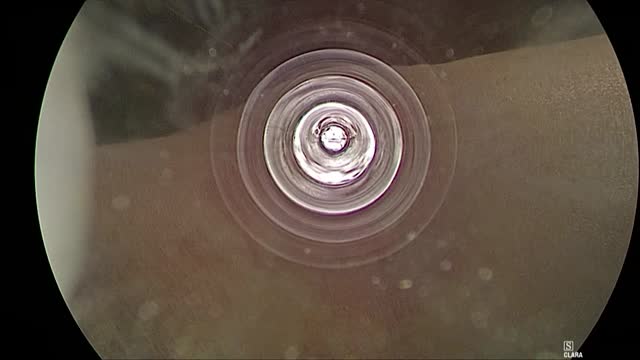

La tiroidectomía endoscópica, utilizada principalmente en países orientales, podría ofrecerse en centros de referencia de nuestro país. Se accede a la región cervical con dos puertos de entrada axilar y uno periareolar. Como referencias destacan: el cartílago cricoides (superior), horquilla esternal (inferior) y borde externo del músculo ECM (contralateral). Se procede a completar la lobectomía más istmectomía tiroidea preservando el nervio laríngeo recurrente sin traccionarlo, dado el acceso lateral. Tras 48h sin incidencias, se retira el drenaje y se da el alta. Este abordaje es seguro y factible para muchos cirujanos endocrinos, formando parte de su arsenal terapéutico.